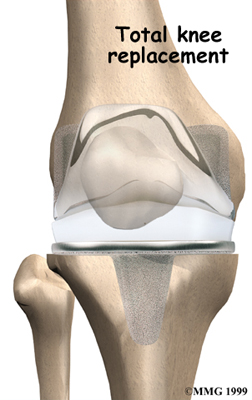

Artificial Knee Replacement

An artificial knee replacement is the ultimate solution for advanced knee OA.

Surgeons prefer not to put a new knee joint in patients younger than 60. This is because younger patients are generally more active and might put too much stress on the joint, causing it to loosen or even crack. A revision surgery to replace a damaged prosthesis is harder to do, has more possible complications, and is usually less successful than a first-time joint replacement surgery.

Related Document: FYZICAL East El Paso's Guide to Artificial Joint Replacement of the Knee